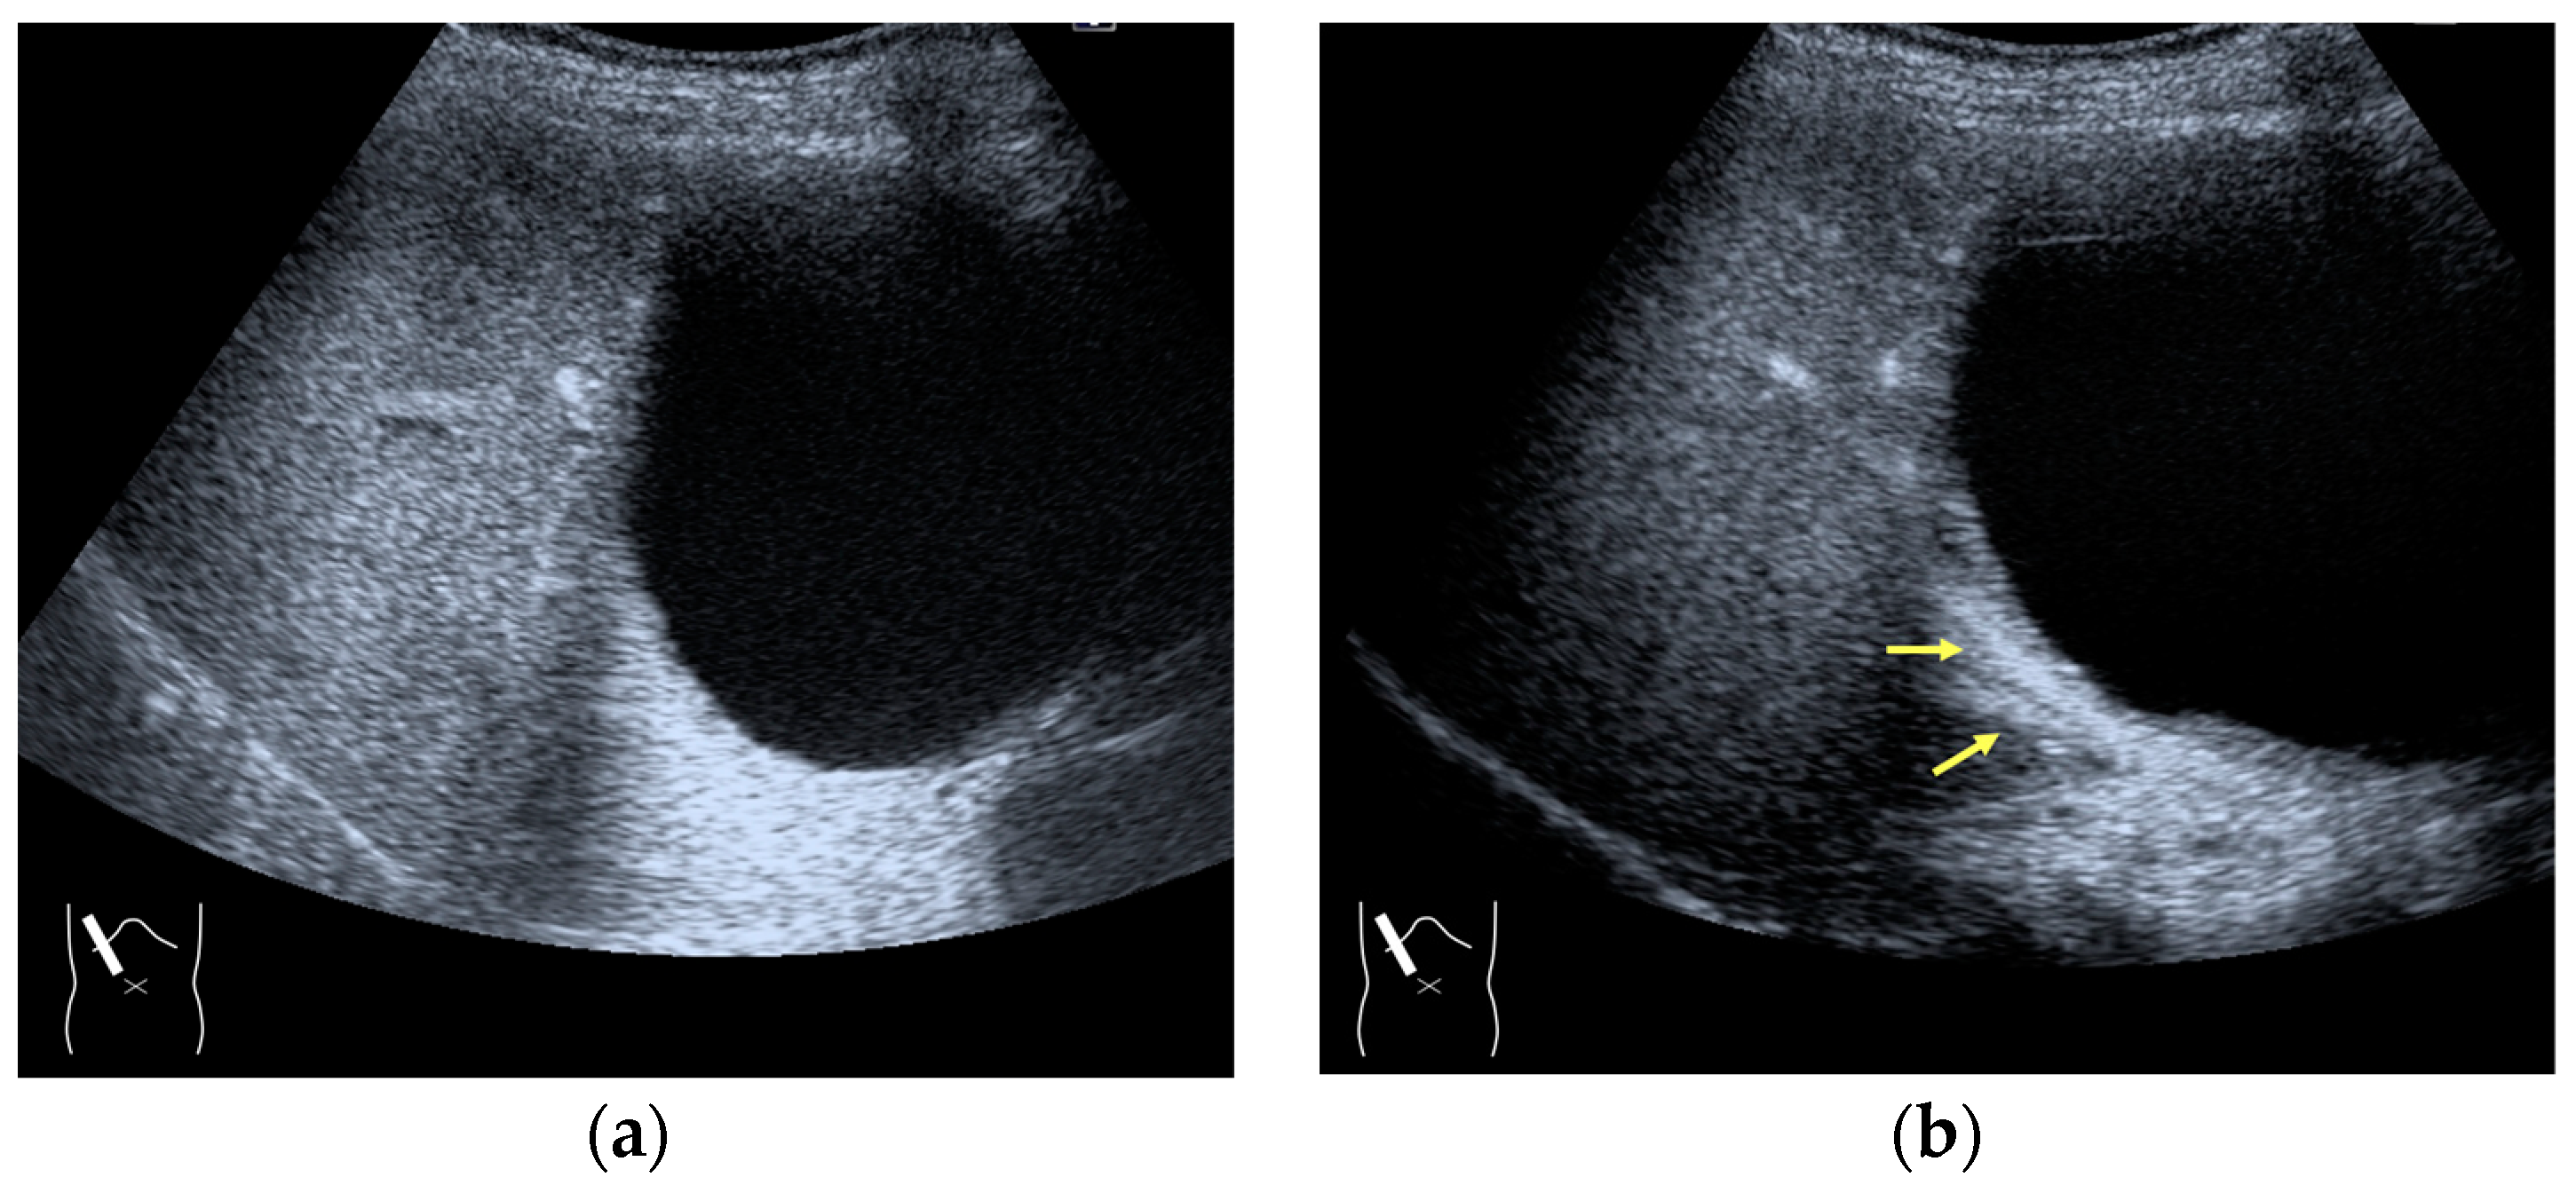

3.2.3. CEUS-Related Posterior Echo Enhancement

CEUS-related posterior echo enhancement (PEE) differs from that of B-mode US. PEE is the most easily recognizable US artifact, and it is characterized by an echogenic band behind a lesion with sonographically different characteristics. In B-mode US, PEE is thought to be secondary to changes in the attenuation of US beams. The area distal to a less attenuating lesion exhibits an increased US intensity and is brighter than it would be without the lesion [60,61]. Posterior echoes are also considered to be strongly related to sound refraction, which occurs when the US beam strikes the interface between two media with different acoustic velocities at an oblique angle of incidence [62]. Whether the US beams converge or diverge depends on the form of the interface and whether the sound path is from a high-velocity medium to a lower-velocity medium or the opposite. The latter condition is thought to give rise to PEE. Aside from these well-known causal factors, there are many other factors contributing to PEE, including reverberation. In brief, PEE remains a multifaced entity featuring complex interplay among sound attenuation, sound refraction, sound reverberation, and other factors. In the clinical setting, hemangioma [63], hepatocellular carcinoma [61], and hepatic cysts are known to cause PEE. We sometimes encounter CEUS-related PEE in daily CEUS examinations. It is characterized by the sudden appearance of a highly echoic zone during CEUS at a location where there was no highly echoic zone in B-mode US (Figure 14). Although this phenomenon’s mechanism of appearance has not been fully elucidated, the most plausible explanation is that many scattered signals emitted from the contrast agent, which rapidly flow into the lesion, interfere with each other inside the stained area, and the reflected time-delayed signals return to the transducer with a certain delay, resulting in the appearance of a highly echoic zone behind the lesion. The precise mechanism of CEUS-related PEE is a problem to be resolved in the near future.

Figure 14.

Posterior echo enhancement appearing during CEUS. (a) Gray-scale US of the case (arrows). (b) CEUS image of the lesion (focal nodular hyperplasia) (arrows). (c) CEUS image of posterior enhancement (arrow heads). Posterior echo enhancement appears immediately after the mass is rapidly and homogeneously enhanced. (d) Reasonable explanation of this phenomenon. Many scattered signals emitted from the bubbles that rapidly enter the mass lesion interfere with each other inside the stained area, and these scattered signals return to the transducer with a certain time-delay. These time-delayed signals are displayed as a PEE. Black circle: mass lesion; small blue circles: CEUS bubbles; red solid line: ultrasound beam; red dashed line: ultrasound is expected to travel; red arrows: reflection between bubbles.